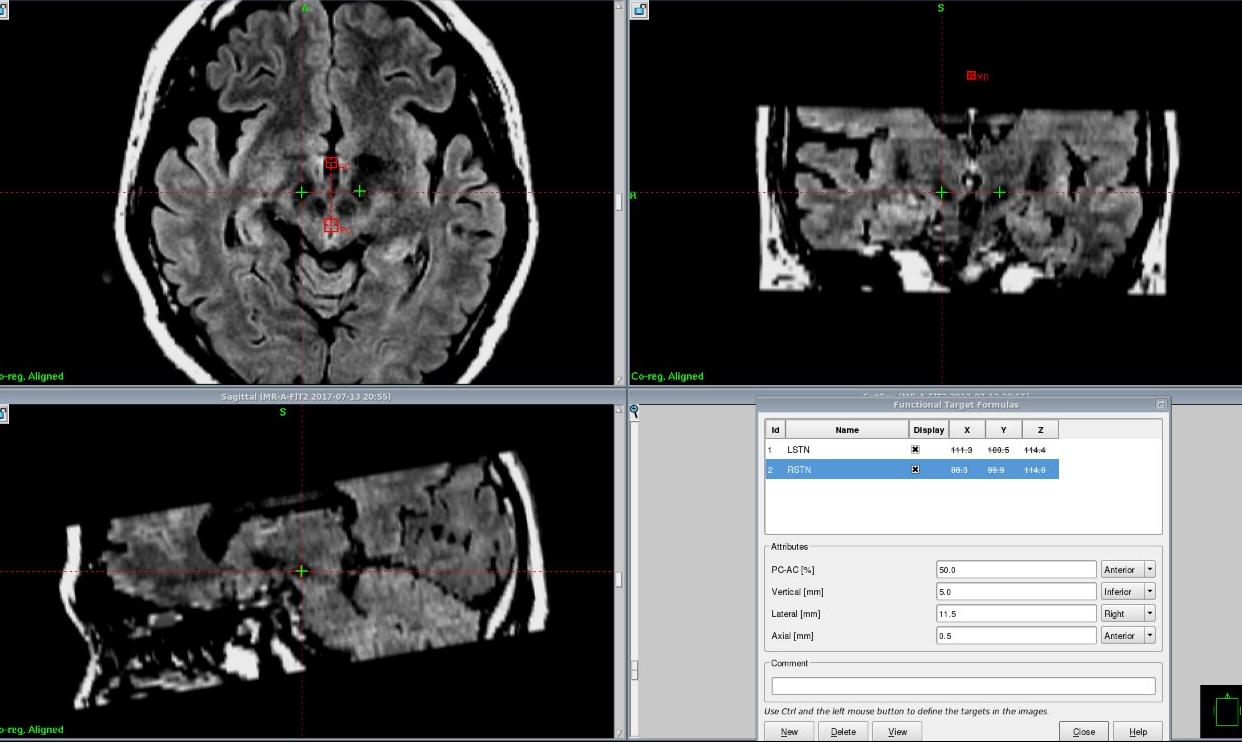

第二:根据病人的特点选择相应的靶点核团。帕金森病电极放置的手术靶点有VIM核、GPi核、STN核和PPN核(大脑中间像黄豆大小的脑细胞聚集体),只有根据每个患者自身表现,选择相应的核团,才能取得最佳效果。

第三:靶点定位非常准确。帕金森病的手术靶点常用是GPi核和STN核(大脑中间像黄豆大小的脑细胞聚集体),一般传统的影像学看不到核团,所以医生一般根据国际上通用的坐标和经验进行电极的放置,有时会出现电极位置偏差。我们中心已经摸索出最好的核磁共振检查方法,能够看到每个患者的核团,根据每个患者的核团情况进行放置电极;同时在手术中我们采用最先进的细胞放电方法探测核团位置;在做手术的同时,我们还用手术当中核磁共振扫描确保电极放置位置准确,通过这几种方法,保证靶点非常准确放置在核团里面,取得最佳效果。